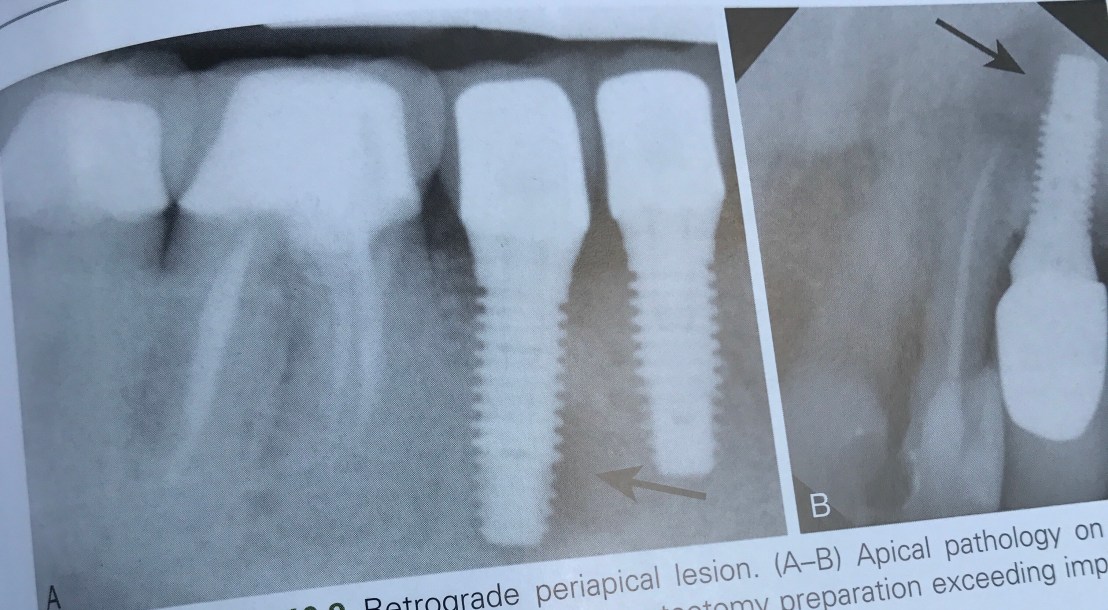

บทที่ 10 ข้อแทรกซ้อนหลัง Surgery

ในเคสที่ฝังแล้ว เกิดปัญหา Root proximity ที่มากเกินไป การ recall เป็นระยะหลังทำ เป็นสิ่งจำเป็นมาก เพราะอาจลงเอยด้วยการมี lesion และฟันตาย